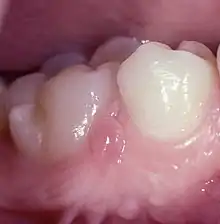

Retrocuspid papilla (RCP) is a small elevated nodules mostly behind the lower canine teeth in humans(Fig.1,2).[1] It is sometimes associated with reactive arthritis.[2]

The lesions are bilaterally situated in the attached gingiva or close to the border of the mucosa lingual to the two mandibular canines (Fig.1).[6]

However, they could in a few individuals also be seen simultaneously in the molar region and on the lingual side (Fig.2).[7] They were 2–3 mm wide and high and covered with normal mucosa. Their tips were erected or could be folded down, mimicking the entrance of a periodontal abscess, but no duct was present.